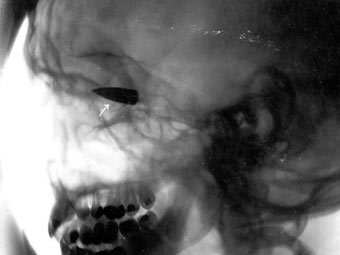

Рентгеновский снимок пули в голове. Иллюстрация с сайта trauma.org

84-летний аргентинец пять раз выстрелил себе в голову и один раз в грудь, однако на момент прибытия в больницу даже не потерял сознание. Об этом в среду сообщает The Australian.

Племянник пострадавшего услышал выстрелы и вызвал на место происшествия полицию. Раненого старика увидели сидящим в кресле. Рядом с ним лежал пистолет 22 калибра. Аргентинец не мог говорить, однако нормально объяснялся жестами.

По прибытии в больницу аргентинец впал в кому и сейчас находится в критическом состоянии. Рентген показал, что все шесть пуль застряли в теле неудачливого самоубийцы.